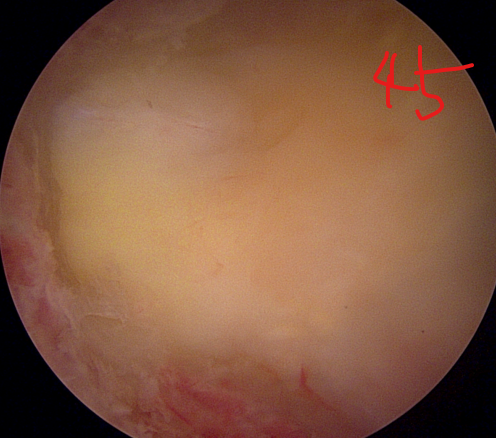

양방향 척추 내시경을 통한 다발성 척추 협착증의 치료 [온종합병원 척추센터 우영하 소장 ]

- 계획: 양방향 척추 내시경은 미세한 카메라와 도구를 사용하여 척수와 주변 신경 구조를 정밀하게 시각화할 수 있습니다. 이를 통해 정확한 진단을 내릴 수 있으며, 각 환자에게 맞는 개별적인 수술 계획을 수립할 수 있습니다.

- 소형 절개와 미세한 수술: 양방향 척추 내시경은 작은 절개를 통해 수술을 수행할 수 있습니다. 이는 환자의 회복 기간을 단축시키고 합병증의 위험을 줄입니다. 또한, 미세한 도구를 사용하여 정교한 조작이 가능하므로 척추 근육과 조직을 최소한으로 손상시키면서 치료할 수 있습니다.